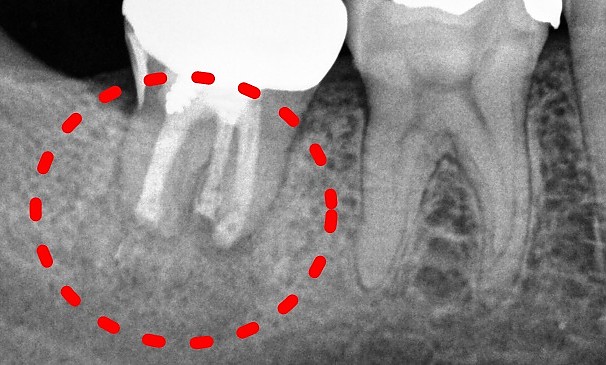

강OO님 전후사진 | 치료 기간 : 2주

치료 전

치료 후